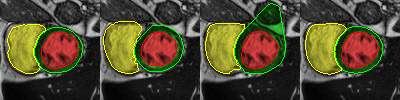

Careful inspection reveal that errors are not uniformly distributed. Interestingly, conv-deconv and U-Net produce accurate results on most slices of each 3D volume as illustrated in the first two rows of Fig. 2. That said, they often get to generate a distorted result for 1 or 2 slices (out of 7 to 17) which end up decreasing the Dice score and increasing the Hausdorff distance. This situation is shown in rows 3,4, and 5 of Fig. 2. Overall, the right ventricle is the most challenging region for all three methods. It is especially true at the base of the heart, next to the mitral valve where the RV is connected to the pulmonary artery. This is illustrated in the last row of Fig. 2.